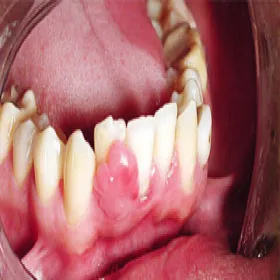

Nadziąślak, epulis

Nadziąślak